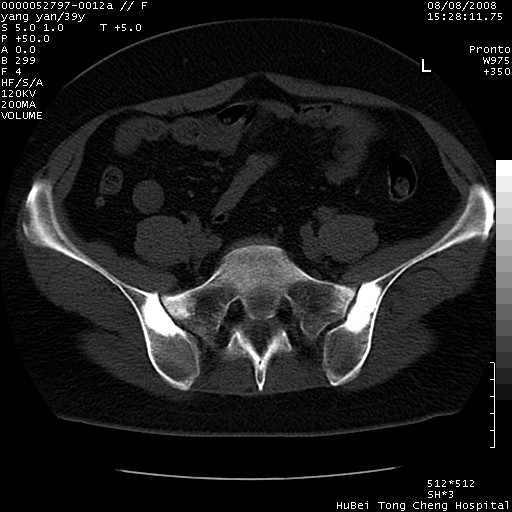

患者 女,39岁。因外伤检查,偶然发现。

典型!双侧骶髂关节致密性骨炎。

典型!病变主要累及双侧髂骨。常见于育龄期妇女。

致密性骨炎,一般不跨越关节面,可是这个骶骨关节面也有硬化。

髂骨致密性骨炎系一种以骨质硬化为特点的非特异性炎症,有高度致密的骨硬化现象,尤其以髂骨下2/3更为明显,但关节间隙则无改变。因位于骶髂关节,且该关节症状明显,故又称之为“骶髂关节致密性骨炎”。 本病90%以上为中年女性,以妊娠后期、尤其分娩后为多见,亦可见于尿路或女性附件慢性感染后,或盆腔内其他感染。此外,臀骶部的外伤亦可诱发或引起本病。  妊娠、分娩及外伤均可引起骶髂关节韧带的撕裂而易使局部的血供受阻。因此早期局部呈现充血、水肿及渗出增加等,渐而局部出现增生与变性反应,随着胶原纤维的致密化而向硬化演变;血管形成厚壁血管,易闭塞而引起髂骨耳状面处缺血和缺氧,骨质呈现硬化性改变,以致手术时局部出血较少。骶髂关节囊壁显示纤维增生、弹性降低及松动样改变。继发于盆腔内炎症者亦出现相类似的病理改变,可能系细菌内毒素作用所致。